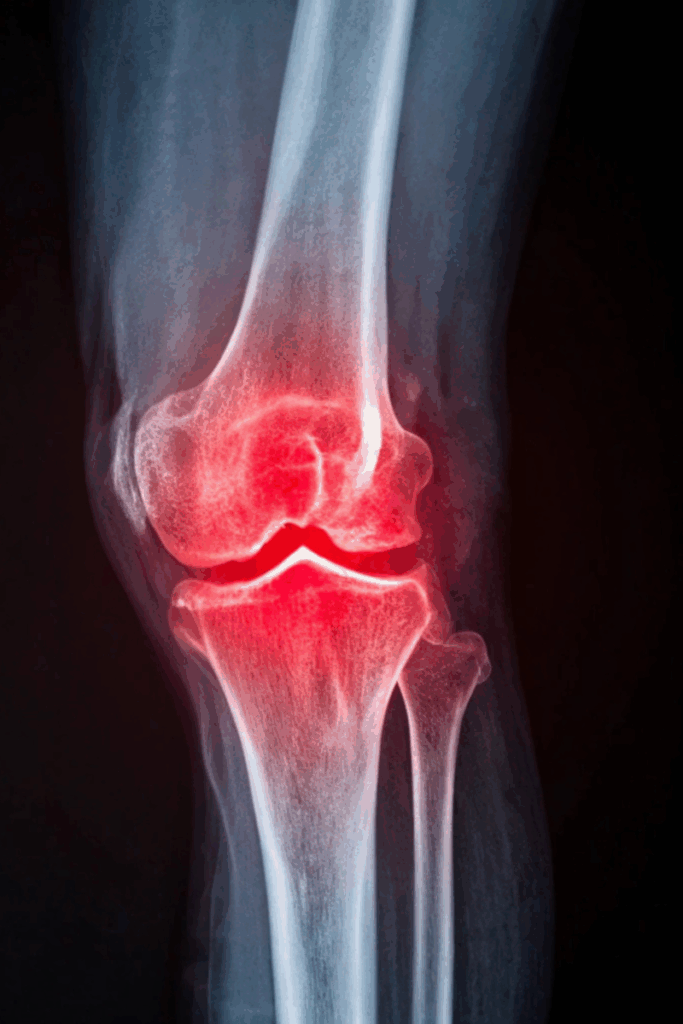

Winter knee pain is extremely common in Maine, especially once temperatures start to drop. Many people notice more stiffness, soreness, or swelling throughout the season, but most don’t understand the real reason behind it. Much of this discomfort comes from the way cold weather changes the fluid inside your joints. This post breaks down the science in simple terms and explains what you can do to keep your knees feeling strong all winter.

Inside every joint, including your knees, you have synovial fluid. It works like oil in a machine by allowing your joints to glide smoothly. When the temperature drops, the fluid becomes thicker and moves less easily. Your muscles also tend to tighten up, and blood flow slows down in cold weather. All of these changes create a heavier, stiffer feeling in your knees. If you have arthritis, an old injury, or chronic inflammation, these cold-weather effects can feel even more intense.

Your knees are involved in almost everything you do, from walking and climbing stairs to getting in and out of the car. When joint fluid thickens in the cold, movement becomes harder and less smooth. Many people notice that their knees feel stiff when they first stand up, take longer to warm up during activity, or become sore after sitting for long periods. You might even notice more clicking or popping. If you already live with arthritis, the cold can trigger stronger inflammation, making everyday movement feel more uncomfortable.